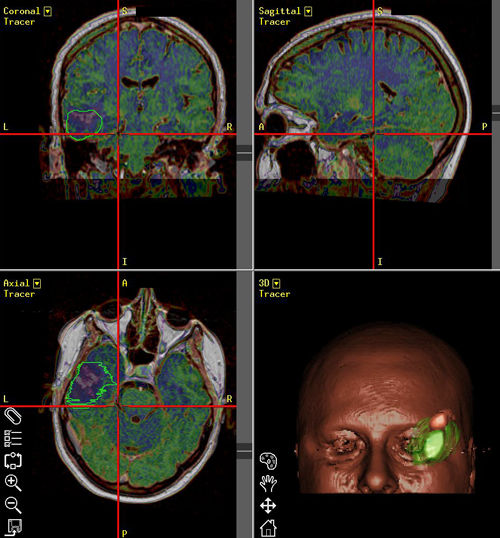

Navi13

Νευροπλοήγηση σε ασθενή με όγκο εγκεφάλου. Όγκος με πράσινο, αγγεία με κόκκινο και μπλέ, μετωπιαίος κόλπος με γαλάζιο.